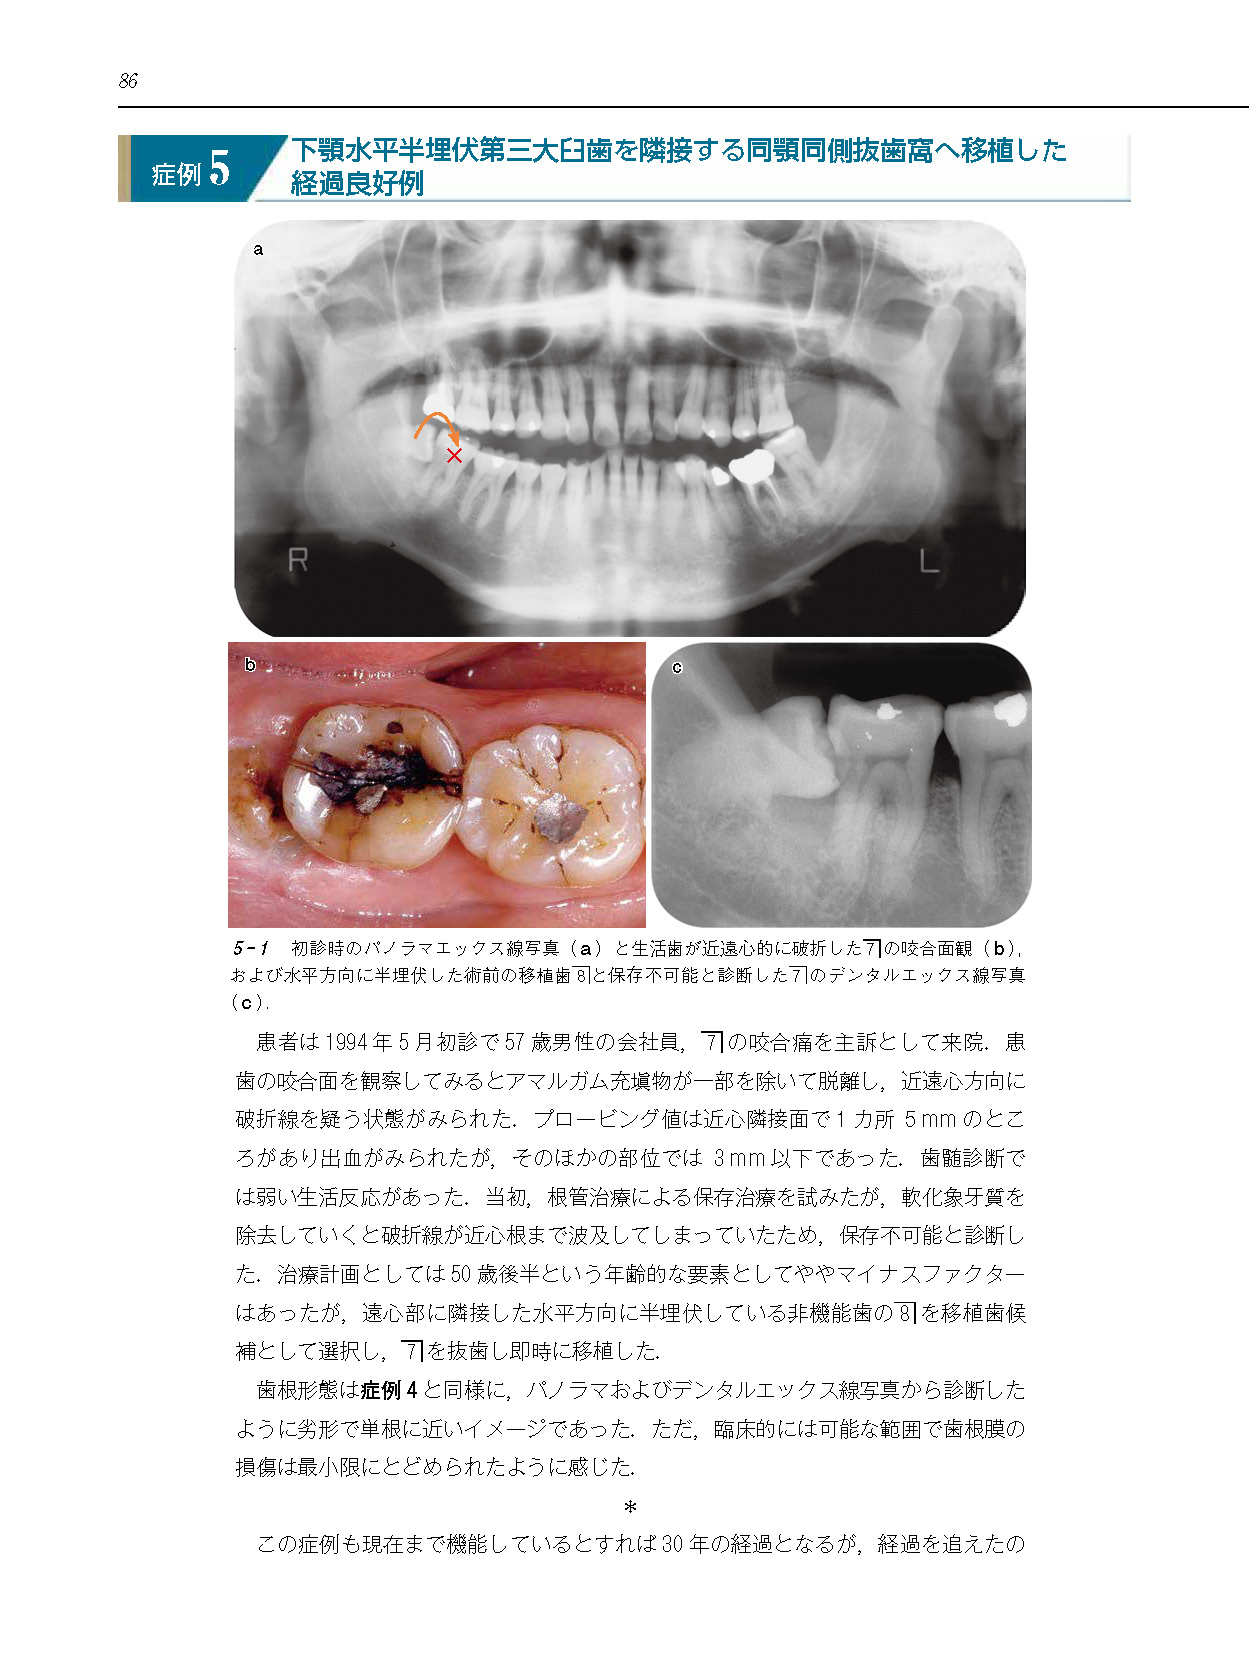

インプラント時代に見直す 歯の自家移植を始めよう!―歯根完成歯の長期経過症例から考える要点―